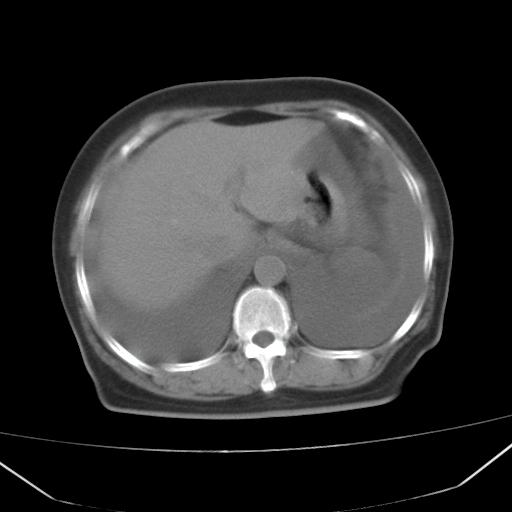

以下是引用jiangjing在2008-4-20 10:43:00的发言:[br]结合病史支持 冠心病[冠状动脉钙化],心功能不全,肺淤血、肺水肿,双侧胸腔与斜裂积液

以下是引用lijuanln在2008-4-19 23:05:00的发言:[br]两侧胸腔积液,肺水肿[br]心包积液[br]提示心衰